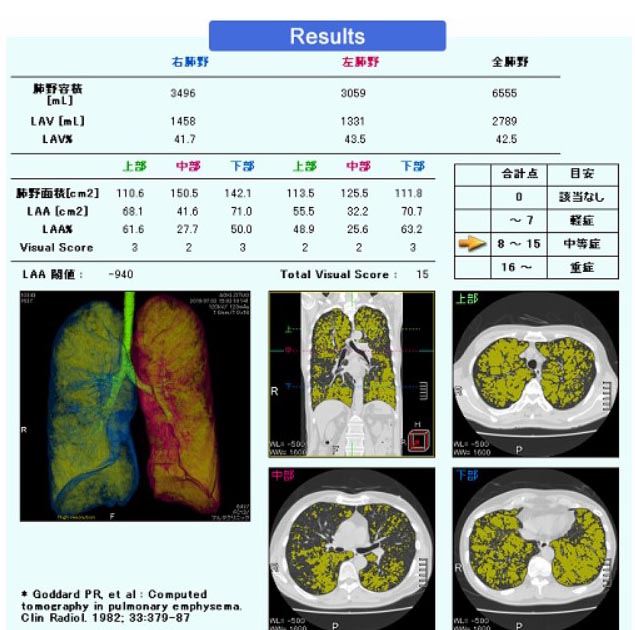

- COPD・肺気腫